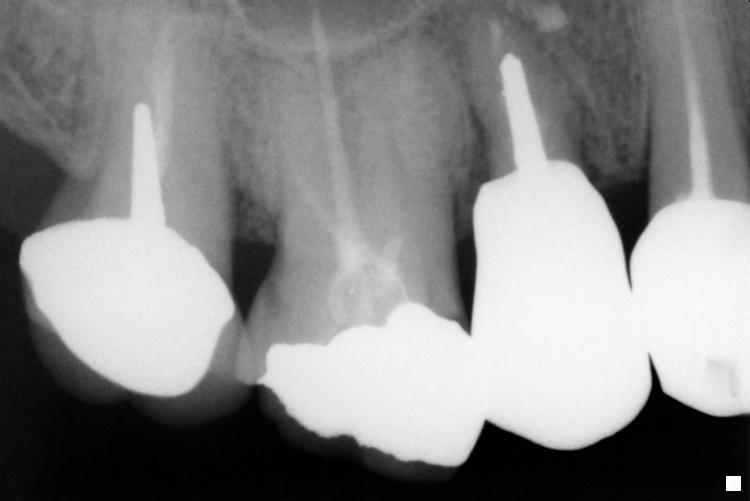

IO000001.jpg

2020-07-28 14:25 72K